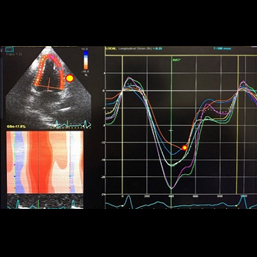

ところが、当院のスペックルトラッキング法、心臓超音波機器を用いることにより、24時間~48時間前の発作をまるでタイムマシンのように追跡することができるケースも出てくるようになりました。

開業以来、複数名の方が当院で診断を得られています。その診断に基づいた治療により、症状も劇的に改善しています。この医療機器を用いても保険診療ですので、患者様のご負担は他のエコー機器の場合と同様です。心電図に変化がなくても、急性心筋梗塞を発見し得たケースもあります。この最新の超音波機器が当院の特徴です。

1.撮影

2.撮影したエコーを解析